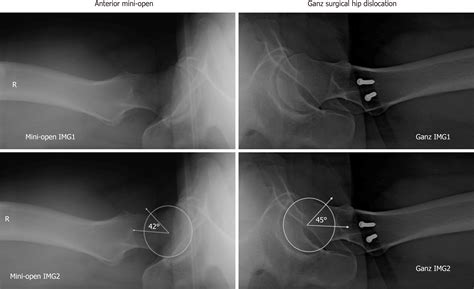

If you suspect you have Cam Impingement Hip, a physical examination is the first step. An orthopedic specialist will perform specific tests, such as the FADIR test (Flexion, Adduction, Internal Rotation), which is designed to reproduce the impingement and pain. Following this, imaging is usually required to confirm the diagnosis.

• X-rays: Standard views help the doctor visualize the shape of the femur and the degree of the bony prominence.

• MRI or MRA: These scans are critical for evaluating the soft tissues, specifically looking for labral tears or cartilage thinning that might have resulted from the impingement.